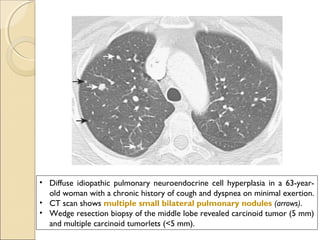

• Diffuse idiopathic pulmonary neuroendocrine cell hyperplasia in a 63-year-

old woman with a chronic history of cough and dyspnea on minimal exertion.

• CT scan shows multiple small bilateral pulmonary nodules (arrows).

• Wedge resection biopsy of the middle lobe revealed carcinoid tumor (5 mm)

and multiple carcinoid tumorlets (<5 mm).